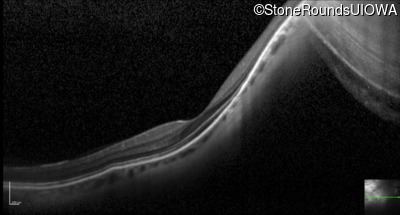

Optical Coherence Tomography - Right - 20/40 +2

Exemplar / OCT Stack